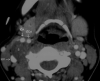

Results: The schwannomas were solitary, well-circumscribed, and medial to the carotid sheath. Seven were hypoattenuated to skeletal muscle on CT with poor postcontrast enhancement, 4 were isoattenuated, and a single lesion showed intense heterogeneous enhancement. At MR imaging, they were heterogeneously bright on T2WI with intense inhomogeneous postgadolinium enhancement. The ICA was displaced anteriorly in 9 patients with a component of lateral displacement in 8 of these patients. The ICA was in a neutral position in 2 patients and posterolaterally displaced in 1 patient. A single patient demonstrated separation of the ICA and IJV. There was splaying of the carotid bifurcation in 4 patients.